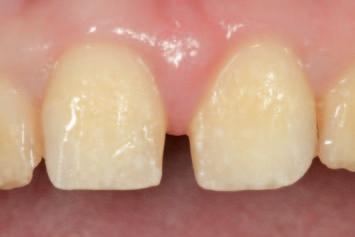

n On the basis of a facially driven smile design, with a patient-centred outcome in mind, contours of the underlying dentition that will impede the achievement of an idealised prosthodontic outcome are identified (Figure 1A) and planned for preparation with a custom digitally designed tooth reduction guide (Figure 1B). This guide is fabricated in a flexible, machinable polycarbonate material (Temp Premium Flexible, Zirkonzahn Srl, Gais, Italy) (Figure 1C).

FIGURE 1: Starting with the end goal in mind, a facially driven digital smile design reveals that the underlying tilting, drifting, rotations and maxillo-mandibular relations of the natural dentition will preclude the development of harmoniously contoured definitive restorations. A tooth preparation guide may be designed and milled at this early stage to assist in conservatively eliminating anticipated interferences, in a highly controlled workflow.

A C B

FIGURE 2: Initial seating of the preparation guide on the dentition allows the clinician to visualise the intended outcome of this treatment step.